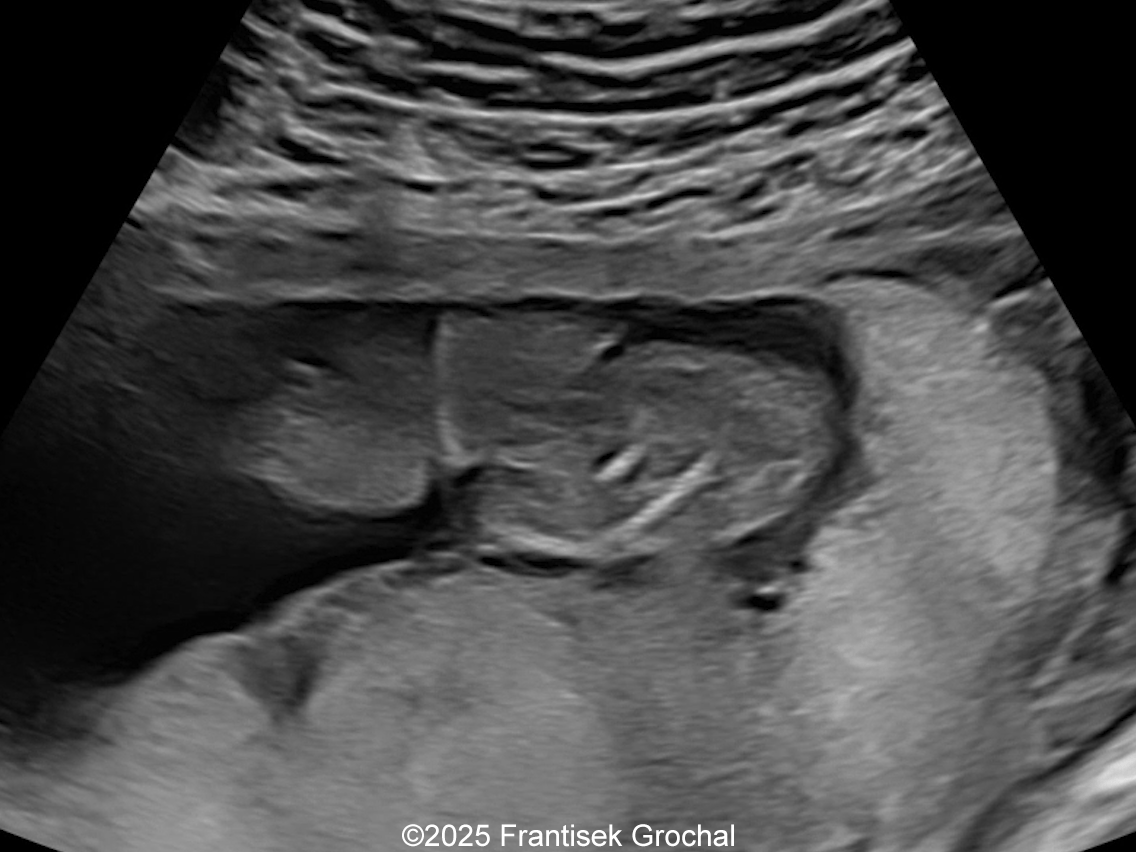

We present a case of Amniotic Band Sequence seen in 21st week of pregnancy. The fetus showed the following findings:

- Constriction of the right thigh by the amniotic band

- Constriction of fetal torso by two strips of amniotic band

Prenatal ultrasound imaging shows thin echogenic bands attaching to both the uterine wall and associated fetal structures. The bands themselves can be difficult to detect, hence the visualization of bands is not required to suggest the diagnosis. Random anomalies that do not follow a pattern should lead the clinician to suspect amniotic band sequence and prompt close evaluation for a causative band [5, 6]. The defects resulting from the bands are categorized into various categories: neural tube-like defects, craniofacial anomalies, limb anomalies, abdominal and thoracic wall defects, and visceral anomalies [7, 8]. The most common findings are those caused by constriction rings in the limbs, which are present in at least 80% of cases. They may vary in depth, involving only the skin, to involving bone and causing edema of the distal limb, extremity asymmetry, pseudosyndactyly, or amputation of limbs or digits [8]. Histologically, constriction bands are composed of fibrous tissue containing fibroblasts covered by squamous cells, which may make them inelastic and produce a ligature effect [9]. Clubfoot deformity of the lower extremity is found in up to one third of cases, probably secondary to the presence of oligohydramnios if there is loss of amniotic fluid [6].